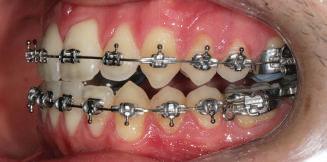

Пациентът постъпи в моята клини ка с наличие на темпоромандибуларен дисфункционален болков синдром, едно странно изместен диск с редукция в дяс ната става, клас II, подклас 2, тесни гор на и долна челюст със струпване, дъл бок овърбайт

орални снимки и снимки на позата, пал пация на мускулите, брукс-чекър, оклу зограми, кондилография, рентгеногра фии, СВСТ и ядрено-магнитен резонанс на темпоромандибуларните стави). Преди началото на ортодонтското лечение всички стари възстановява ния бяха свалени и бяха заменени с дъл госрочни временни от хибридна керами ка. На девитализираните зъби бе прове дено ендодонтско релечение. Индивиду ализиран оклузален сплинт бе направен с цел да се постигне контролирано репо зициониране на долната челюст, като носенето му продължи три месеца до възстановяване на правилната позиция на ставния диск и затихване на орофаци алната болка и дискомфорт в ставата. Брекетите в горната челюст бяха за лепени, за да започне подреждането и нивелирането на зъбите, докато паци ентът все още носеше сплинта. След края на терапията със сплинта бе на правена кондилография, за да се потвър ди триизмерната позиция на долната челюст. След залепване на брекетите в долна

тация на долната челюст. Дъга GUMMETAL с tip-back извивки бе поставена в долната челюст за ниве лиране кривата на Шпее. Случаят бе финализиран с 19x25 SS дъги в горната и долната зъбна дъга за координиране. Преди да се изготви финалният восъ чен моделаж, естетичните и лицеви те характеристики бяха анализирани с помощта на дигитален дизайн на ус мивката, за да се създаде мок-ъп, чии то форма и размери да бъдат одобрени от пациента. Бе оценена фонетиката и бяха заснети лицеви снимки и видеа. Зъ бите бяха изпилени, като препарация та бе изцяло водена от функционалния восъчен моделаж, прехвърлен в устата на пациента. След препарацията восъч ният моделаж бе напаснат и насложен върху препарационния модел и бе фрезо ван от e-max multi bl 1. Циментирането на финалните конструкции бе направе но при изолация с кофердам, следвайки адхезивния протокол. След циментирането бе направено проследяване на оклузията чрез снема не на отпечатъци, монтиране на моде лите в артикулатор в окончателната интеркуспидация и внимателно прове ряване за наличие на блокажи при воде ни движения.

и гингивална усмивка. Започнахме лечението с пълна диагно стика (анамнеза, интраорални, екстра

та челюст 4 минивинта (TADs) бяха по ставени в максилата – 2 в небцето и 2 интрарадикуларно във фронта, с цел да се извърши интрузия на цялата зъбна дъга, да се коригира гингивалната усмивка и да се позволи провеждането на обратна на часовниковата стрелка авторо